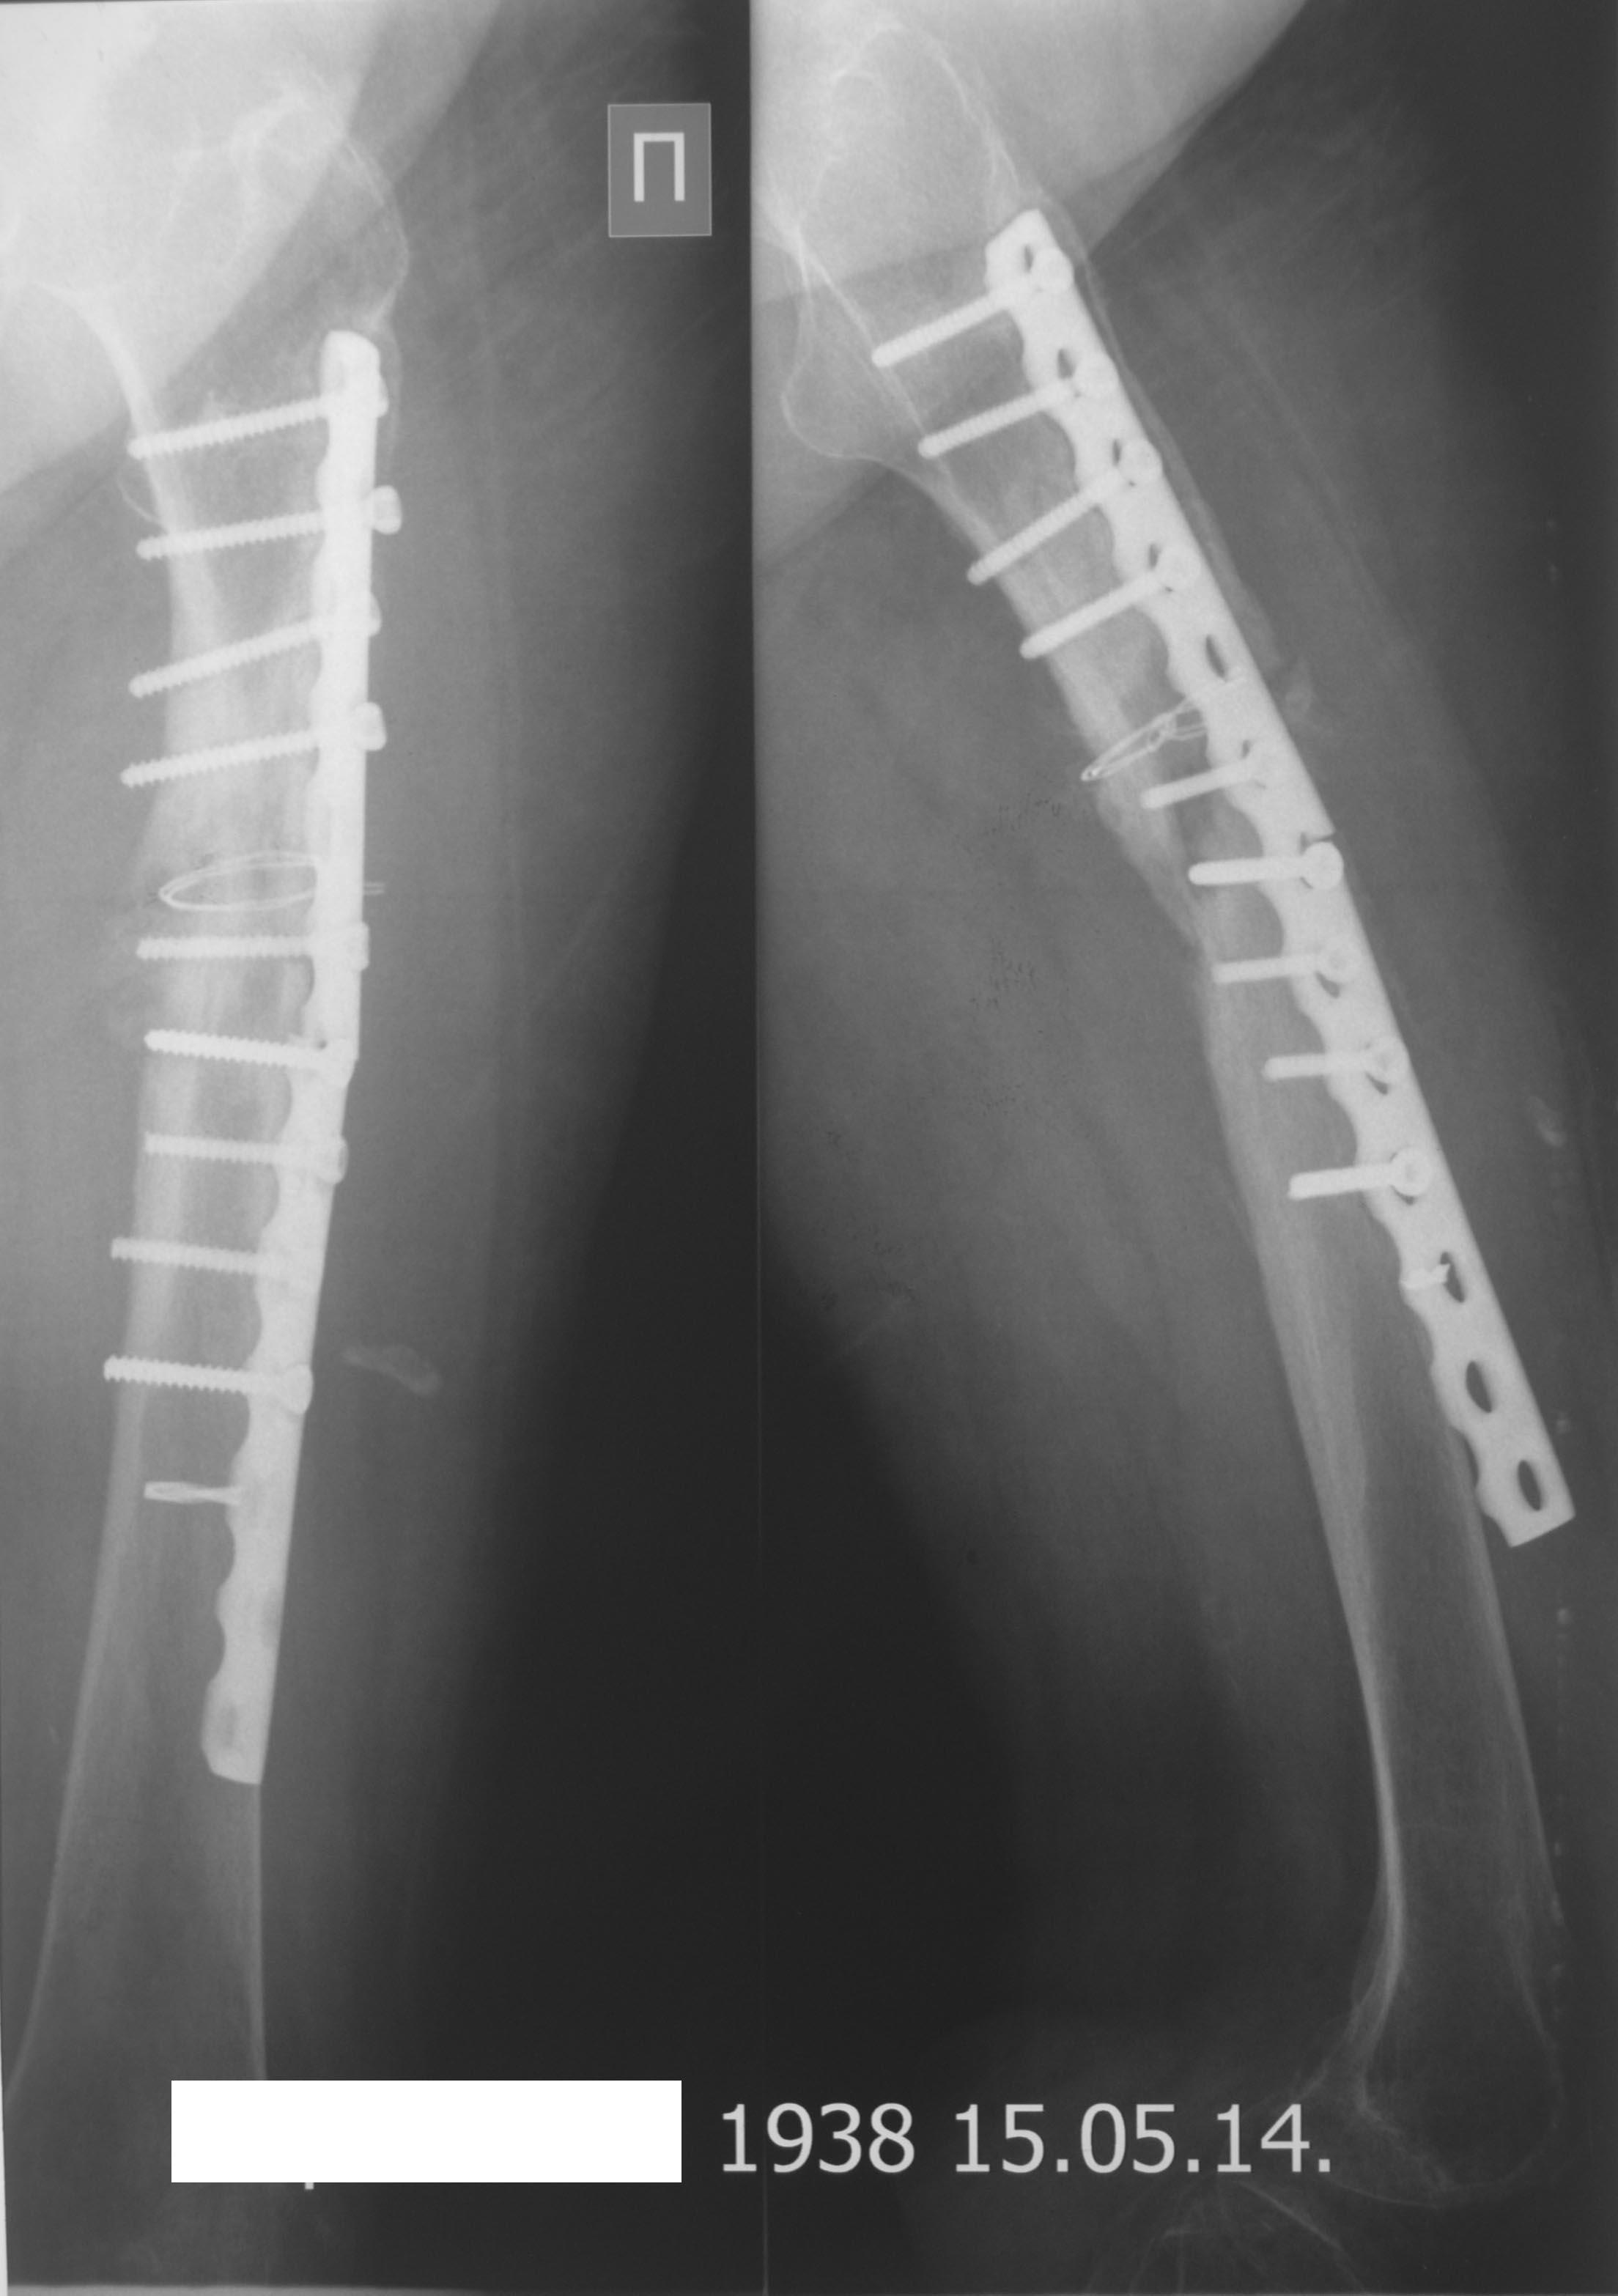

Рентгенограмма бедренной кости

Рентгенограмма после операции.

Было приложено две рентгенограммы

http://weborto.net/forum/pics/2014/05/2729

http://weborto.net/forum/pics/2014/05/2730